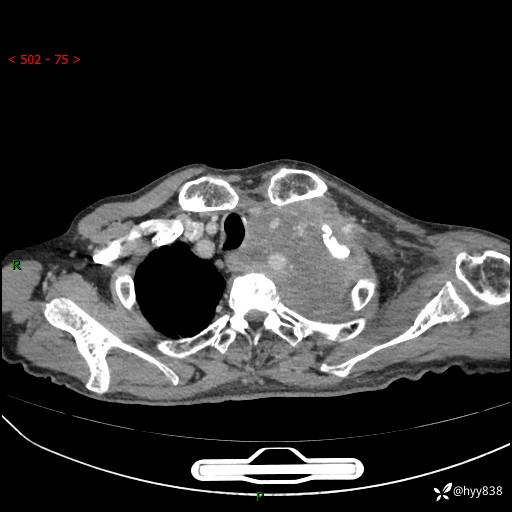

老年男性,气促5月,胸背痛2月。发现肺尖较大肿块,摧枯拉朽之势---结果公布~

现病史:患者于5月前饮酒后突发静息状态下气促不适,无胸闷、胸痛、发热、咳嗽、咳痰等不适,于当地第五人民医院及我院就诊,输液治疗后(具体不详)后气促稍缓解,遂出院后自行口服中草药治疗。近2月出现胸背痛,伴左上肢疼痛、乏力、感觉异常,稍有咳嗽、咳痰,咳黄痰、痰液粘稠,无咳血。为进一步诊治来我院。

胸部CT增强扫描(外院平扫)